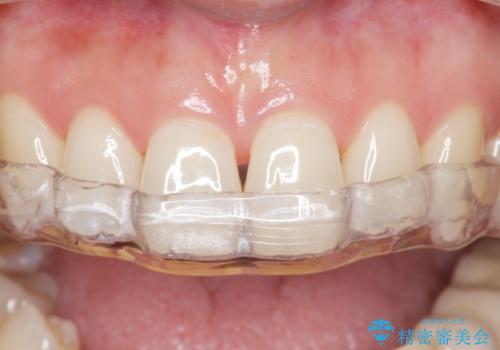

保険のナイトガードに比べて自費のナイトガードは割れる心配がないです。

また噛み合わせの歯と調整をして全体に均一に当たるように調整を行うので噛んだとき力が全体的に分散して歯の負担も減ります。